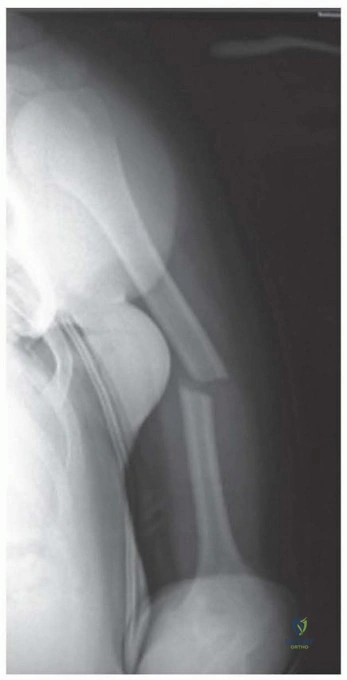

Imaging and Templating

Standard orthogonal radiographs, including an anteroposterior and true lateral of the entire humerus, are mandatory. The imaging must visualize the shoulder and elbow joints to rule out intra-articular extension. Computed tomography is rarely indicated for diaphyseal fractures unless there is suspicion of occult intra-articular extension at the distal humerus.

Clinical & Radiographic Imaging